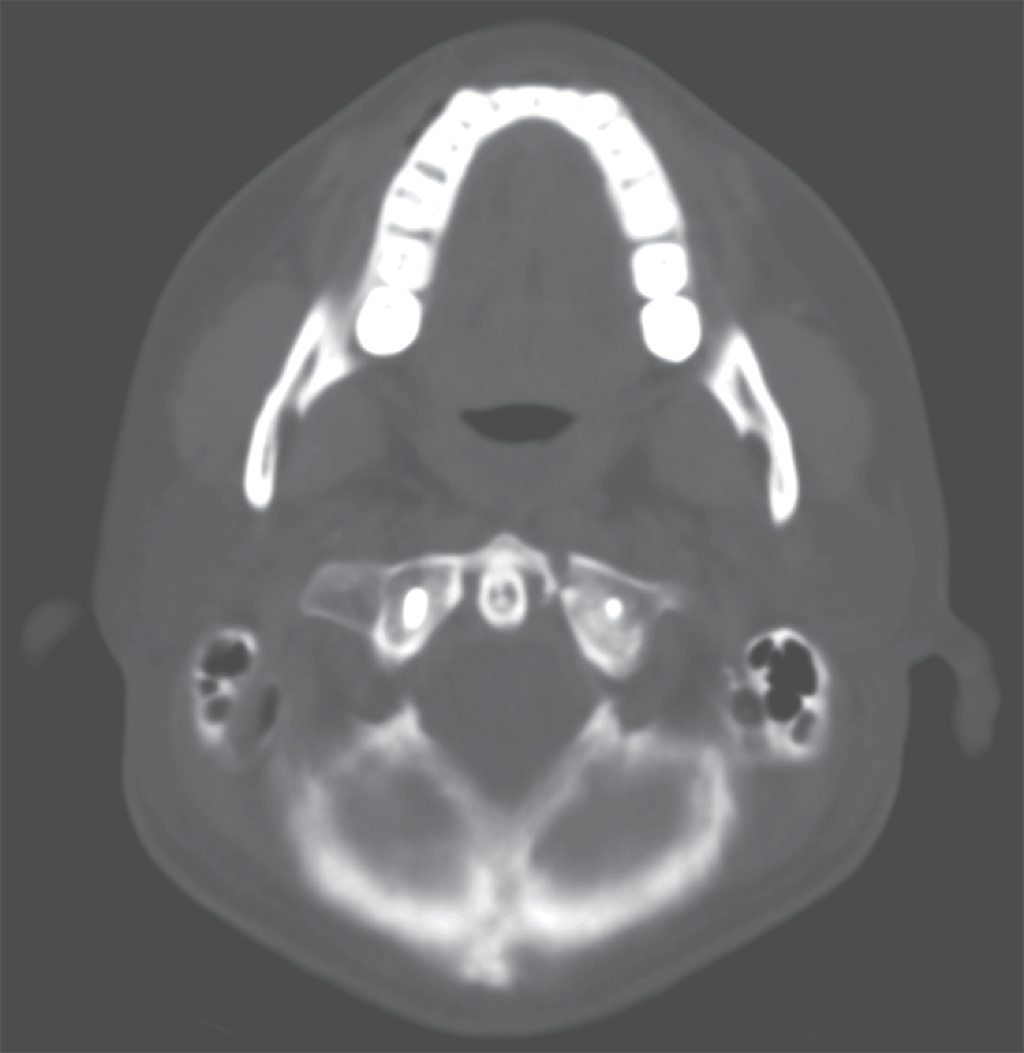

Se presenta el caso de un paciente masculino de 33 años de edad, sin comorbilidades, que acude al servicio de urgencias por presentar cervicalgia de dos semanas de evolución posterior a un accidente en motocicleta. Las radiografías iniciales tomadas en el hospital de primera atención no fueron valorables para diagnóstico; se toman radiografías y tomografía axial computarizada (TAC) de columna cervical (Figuras 1, 2 y 3), diagnosticando fractura de C1 y C7 donde se observa fractura por compresión de C7 AO B2 y C1 con fractura de arco anterior y posterior izquierdo con desplazamiento coronal > 7 mm de la masa lateral izquierda. En la resonancia magnética T2 axial, se observa lesión del ligamento transverso. En resonancia magnética simple se observa fractura de cuerpo vertebral de C7, con compromiso de conducto raquídeo